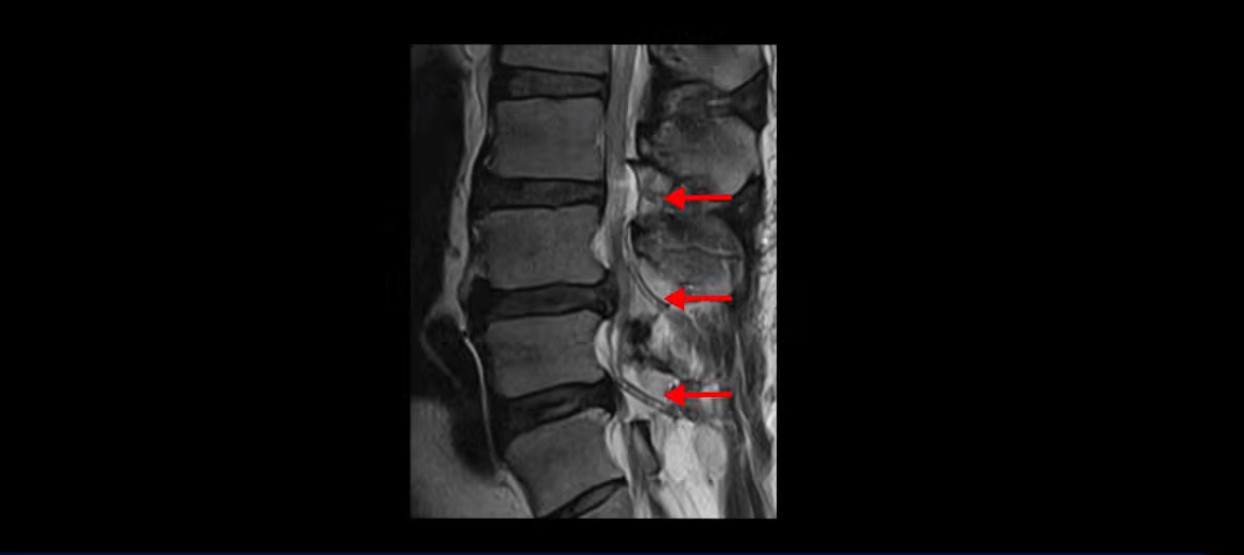

MRI 보면 무려 3마디의 허리 뒤쪽, 후궁 뼈 한쪽을 거의 다 뜯어내고

황색 인대를 대부분 다 걷어냈습니다.

문제는 이 허리 협착이 양손과 양쪽 다리 힘 빠짐의 원인이 아니었기에 수술 후에도 증상이 전혀 좋아지질 않습니다. 그나마 다행인 건 허리 여러 마디를 수술하면서도 나사를 안 박은 겁니다. 수술로 인해 허리 여러 마디에 손상이 생기니까 걷기가 더 어려워져서 결국 저희 병원에 오실 때는 휠체어를 타고 오셨습니다.